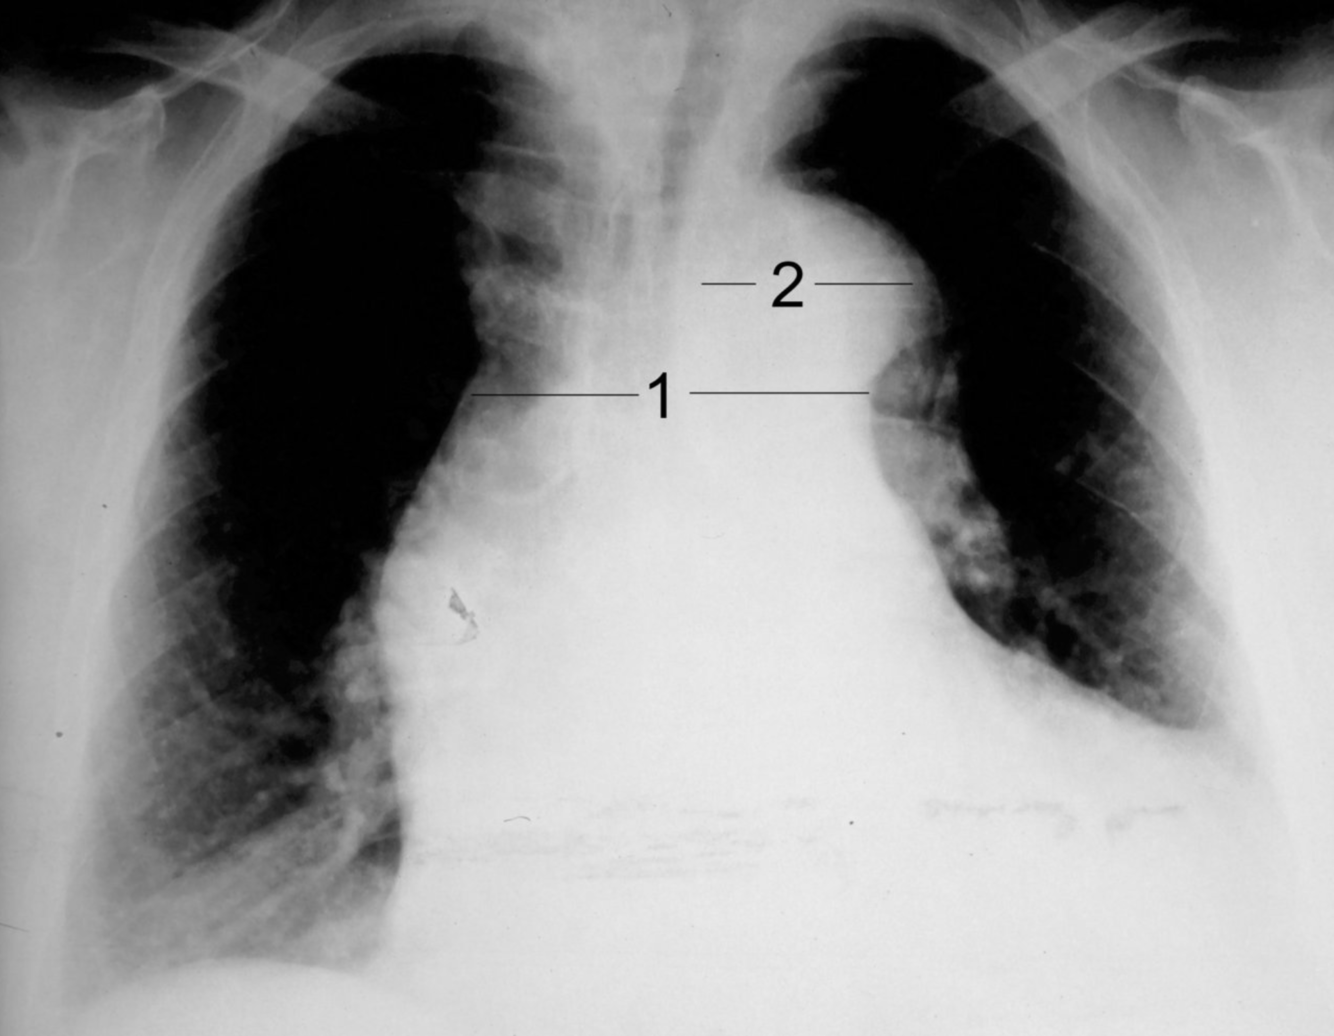

A condition where a tear in the aortic intima allows blood to surge into the aortic wall, causing a split between the inner and outer tunica media, and creating a false lumen.